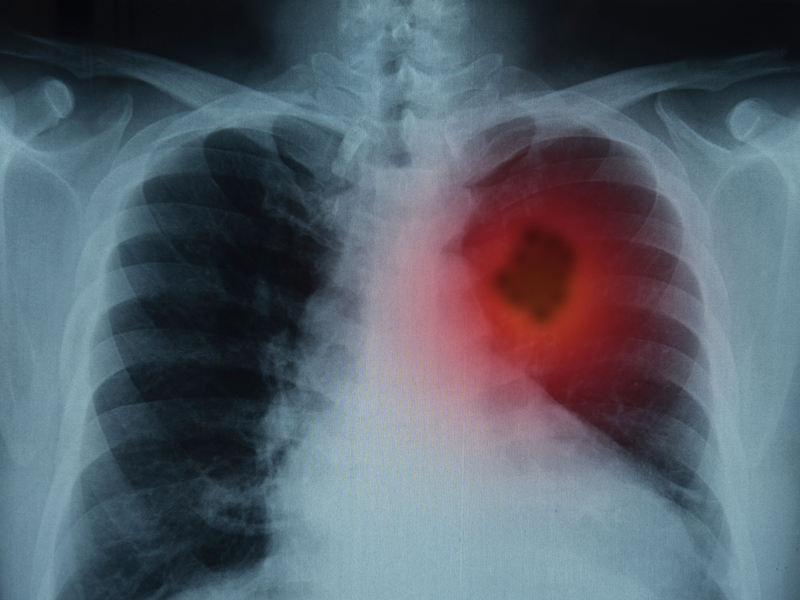

2. 心臟

心臟最怕溫差大。每當氣溫突降時,心絞痛甚至心肌梗死病人就會劇增。因為寒冷刺激可導致人體交感神經興奮,使心率加快、血壓升高、血管收縮、血液循環的外周阻力增加、心肌耗氧量增多,加大了心臟的負荷;更嚴重的時候,冠脈痙攣還會引發粥樣硬化斑塊破裂、血管堵塞,造成心絞痛或心肌梗死的發生。

對策:

注意保暖,尤其要護好頭部、手部、腳部。外出時要戴手套、帽子、圍巾,穿保暖的外套。

適當運動、合理飲食、有心血管疾病者要定時服藥